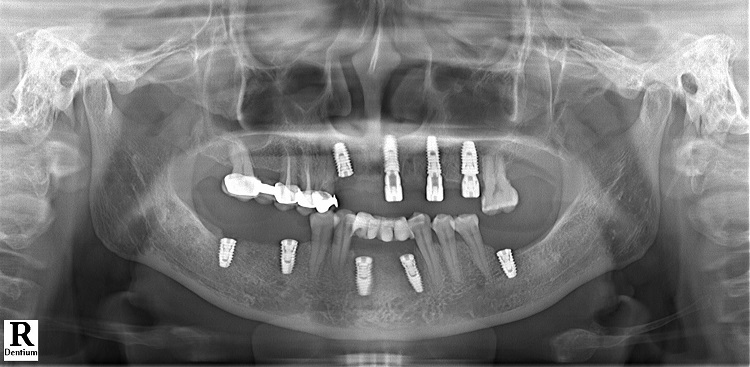

Bác sĩ Vũ Đức Duy - Chuyên gia cung cấp giải pháp cấy ghép implant tại Nha khoa Lạc Việt Intech cho biết, cầu răng sứ hàm trên của cô Đông được lắp sai chỉ định dẫn tới tình trạng hư hỏng nặng, không thể sử dụng. Các răng bị lung lay nhiều, nhiều vị trí bị viêm nha chu, sưng đỏ và có mủ khiến cô đau nhức. Răng hàm dưới của cô Đông cũng bị mất gần hết, chỉ còn lại một vài chiếc răng cửa nhưng cũng trong tình trạng lung lay nhiều.

Với tình trạng của cô Đông, các bác sĩ đã lên kế hoạch điều trị như sau:

- Nhổ bỏ toàn bộ các răng lung lay, hư hỏng.

- Xử lý sạch ổ viêm nhiễm, điều trị nha chu.

- Cấy 4 trụ implant hàm trên và 5 trụ implant hàm dưới.

Bác sĩ Vũ Đức Duy cũng cho biết thêm: “Trường hợp của cô Đông là mất nhiều răng hỗn hợp ở cả 2 hàm trong thời gian dài nên xương hàm của cô bị tiêu lép khá nhiều. Do đó, chúng tôi đã phải ghép thêm xương để có đủ thể tích xương giúp giữ implant vững ổn trong xương hàm. Với công nghệ DCT, chúng tôi đã vừa đảm bảo được quá trình trồng răng diễn ra an toàn, răng sứ trên implant đạt tính thẩm mỹ cao, bền vững.”

Sau 3 tháng chờ trụ implant tích hợp với xương hàm, cô Hoàng Thị Đông đã có một kết quả trồng implant thành công ngoài mong đợi với việc khôi phục thành công 8 răng hàm trên và 9 răng hàm dưới, khôi phục 95% chức năng ăn nhai.